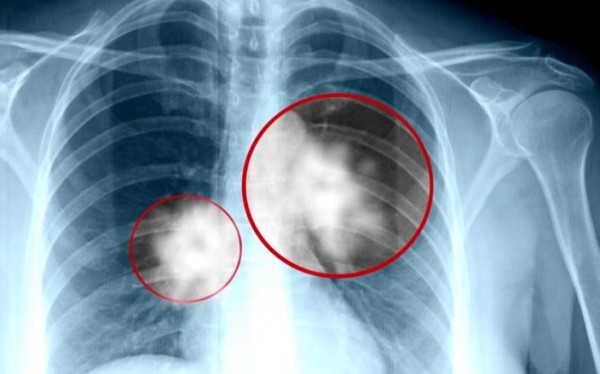

| تطبيق مطوَّر لاكتشاف سرطان الرئة |

قام فريق من الباحثين بتطوير تطبيق يمكنه أن يشخص سرطان الرئة بدقة أكثر من تشخيص الأطباء.وقالت صحيفة lefigaro الفرنسية إن الذكاء الاصطناعي يكتسب أهمية متزايدة في المجال... |